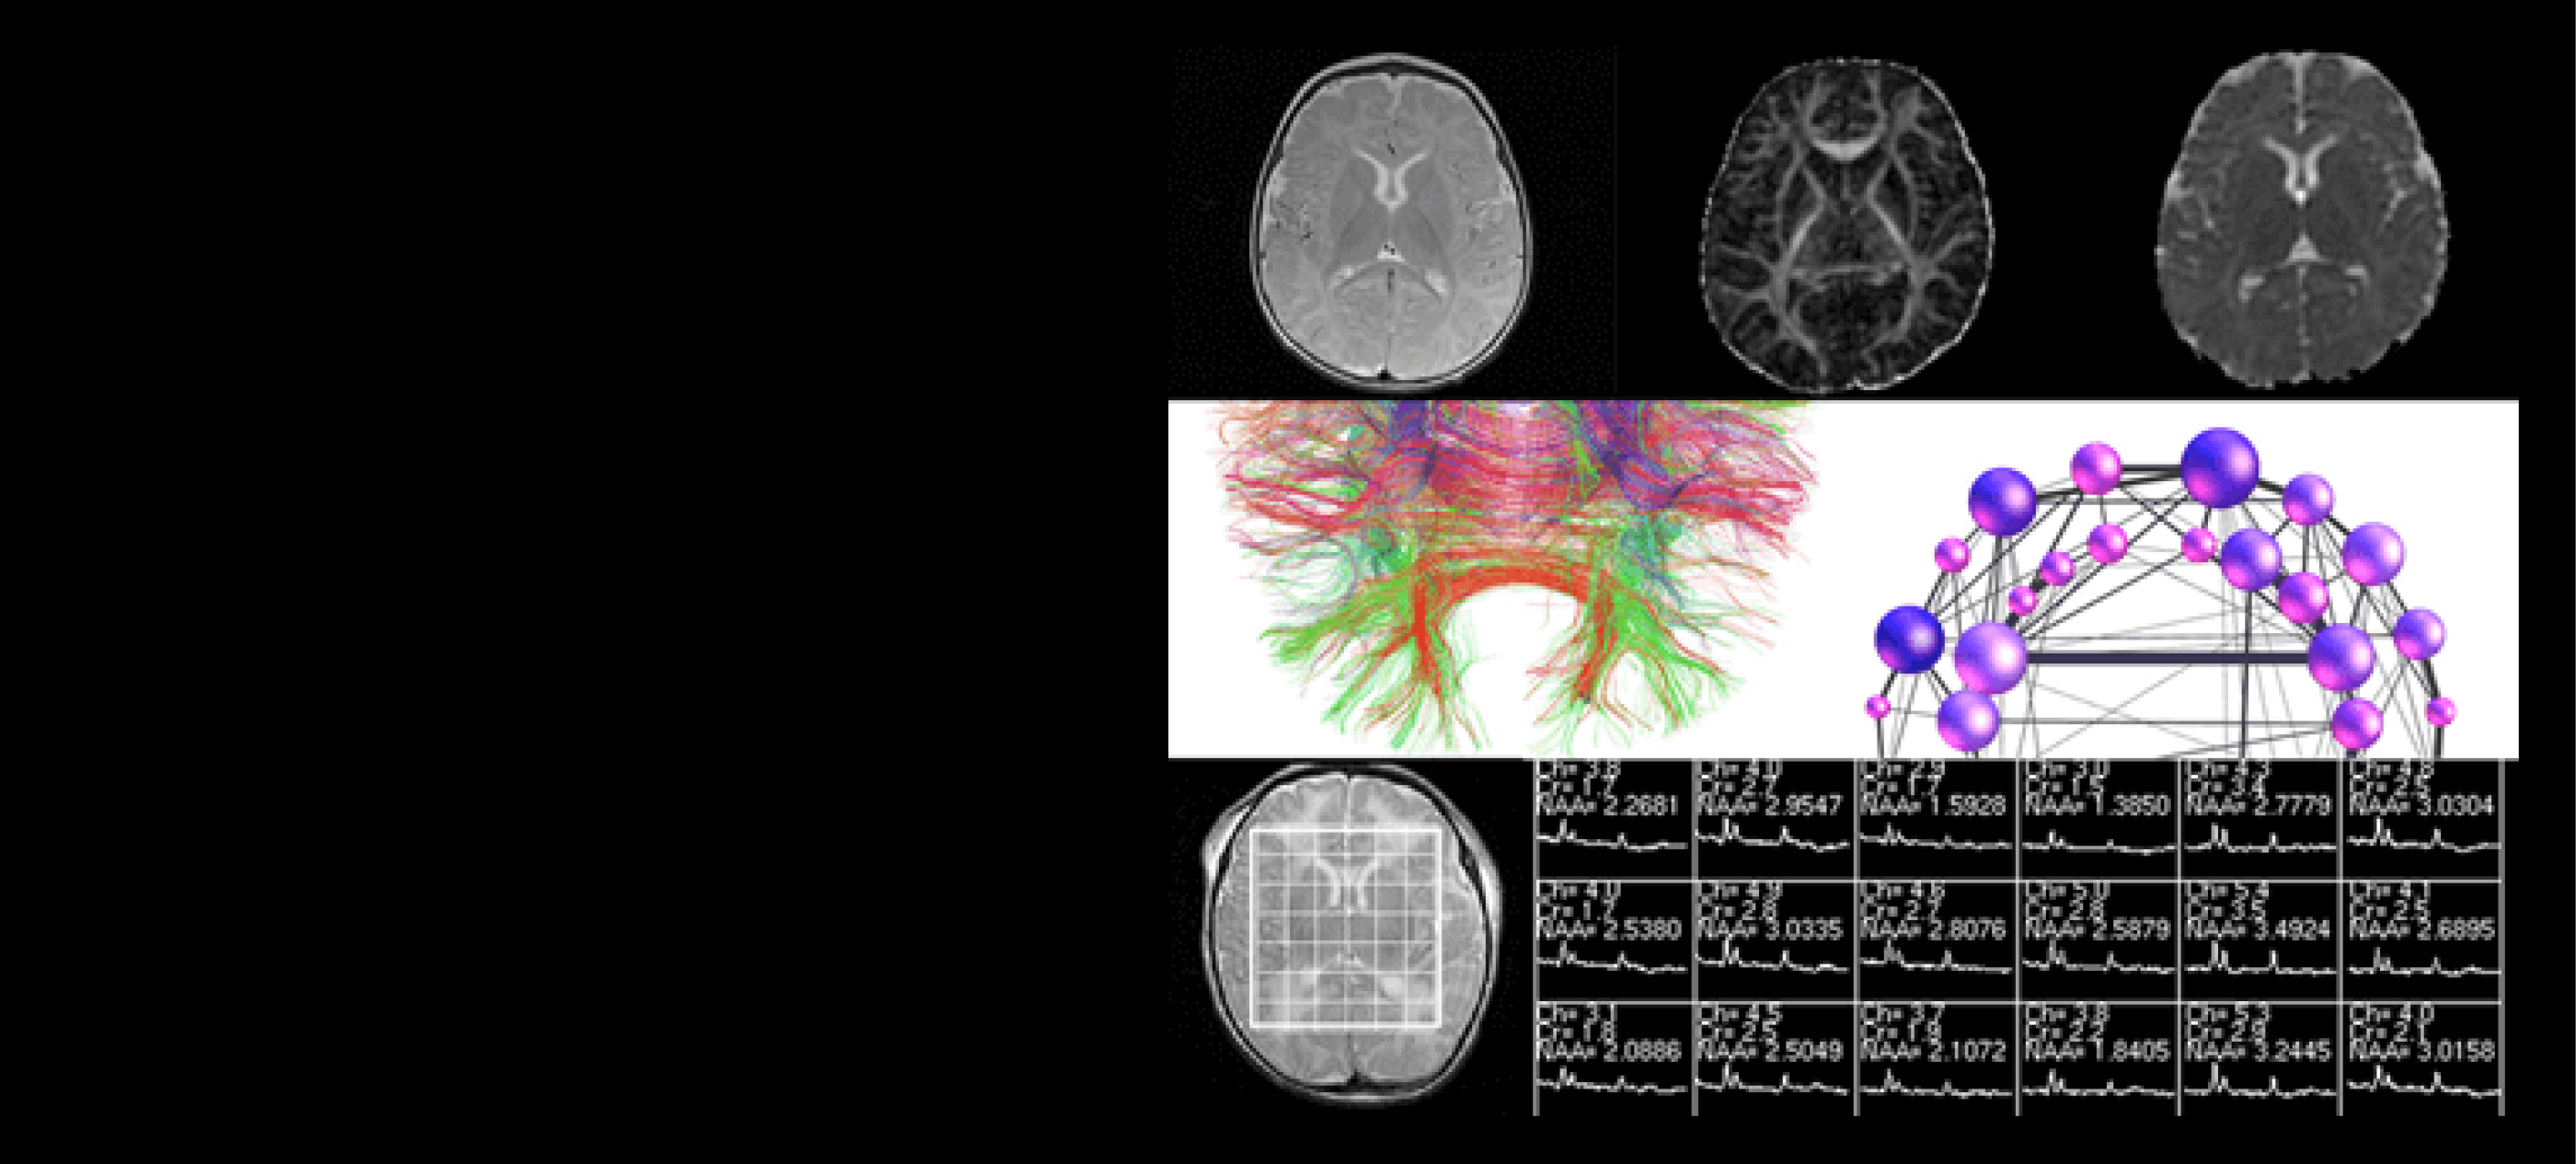

Composite image showing brain MRI scans, fiber tractography, brain connectivity network visualization, and MR spectroscopy data used in neuroimaging and machine learning analysis.

Led by Dr. Duan Xu, the Imaging Research for Neurodevelopment Lab at UCSF focuses on early detection of abnormal development in newborns. To achieve this goal, the researchers in Dr. Xu's lab develop dedicated MRI hardware, pulse sequences, and postprocessing techniques. These methods are then applied to the Premri, Bamri, and Cardiac cohorts to further elucidate neurodevelopment of the neonatal brain.

Can machine learning approaches improve how we gather, learn and predict with our infant MRI data? Our group is working to implement the latest advances in machine learning powered image reconstruction, processing and analysis.

Studies have illustrated prognostic value in determining metabolite ratios between Lactate (Lac), N-acetyl aspartate (NAA), and Choline (CHO) from newborn infants.

The goal of this project is to establish a framework for assessing structural connectivity in the newborn brain at any stage of development, starting with premature neonates, and to…